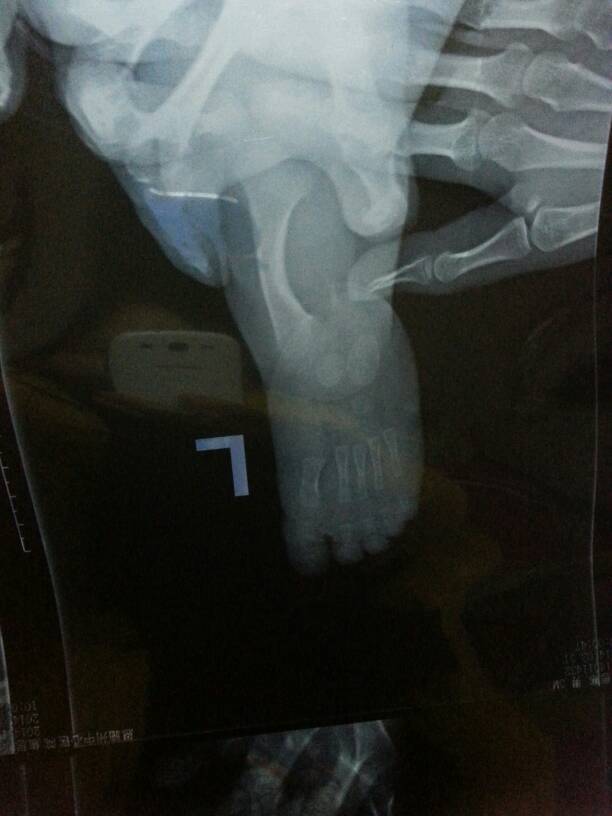

宝宝三个月小腿骨头弯曲不长长怎么办?谁有好办法求指点 点击展开 匿名用户 2014-04-04 11:02 为您推荐: 其他回答 病情分析: 这位朋友你好,考虑缺钙 指导意见: 你好,如果活动无明显障碍,建议检查微量元素,考虑缺钙,建议补钙治疗 匿名用户 2014-04-04 12:09 相关问题 提问:3个月宝宝小腿骨头弯曲怎么办? 左腿疼的没办法入睡,按摩也没用了连小腿那骨头都疼了 请问医生有没有什么办法能缓解,每天睡两三个小时 宝宝已经六个多月了他小腿接近脚踝的位置有点弯曲,有儿科保健医生说是缺钙,有权威专家说是生理性弯曲